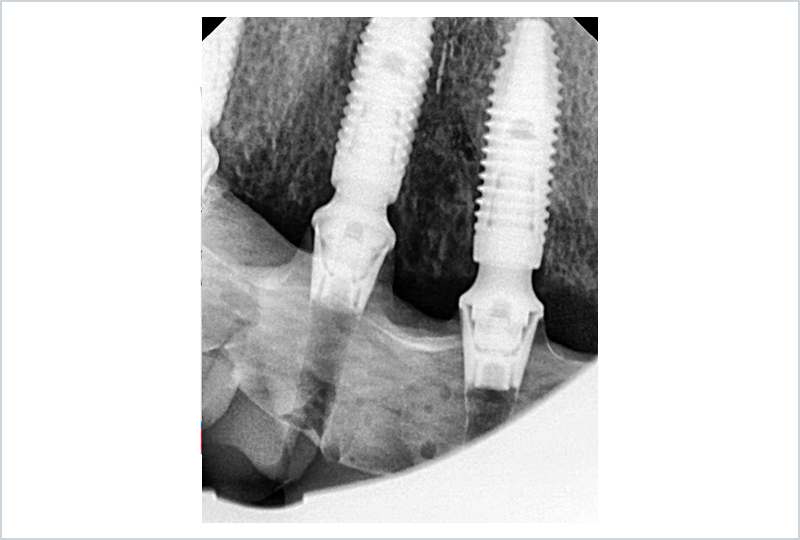

La barra, fresata in materiale metal-free su fresatore a 5 assi, sarà la trave portante della protesi, assemblata e incollata sul modello stampato (Figura 22). L’accoppiamento tra barra e impianti è affidato a TiBase Custom-Interface (IPD Dental Group / AbutmentCompatibili.com). I TiBase sono incollati con OT-Cem (Rhein83) sulla chiave in gesso di validazione finale per garantire la totale passività della struttura sia in laboratorio che sul paziente (Figure 23, 24). La consegna e la validazione finale avvengono con il serraggio della vite più distale e l’osservazione clinica della staticita’ struttura, seguita dal classico check radiologico mirato. (Figure 25, 26 e 27).

Consegna e RX controllo

Fig. 26, 27

Consegna e RX di controllo

Fig. 27